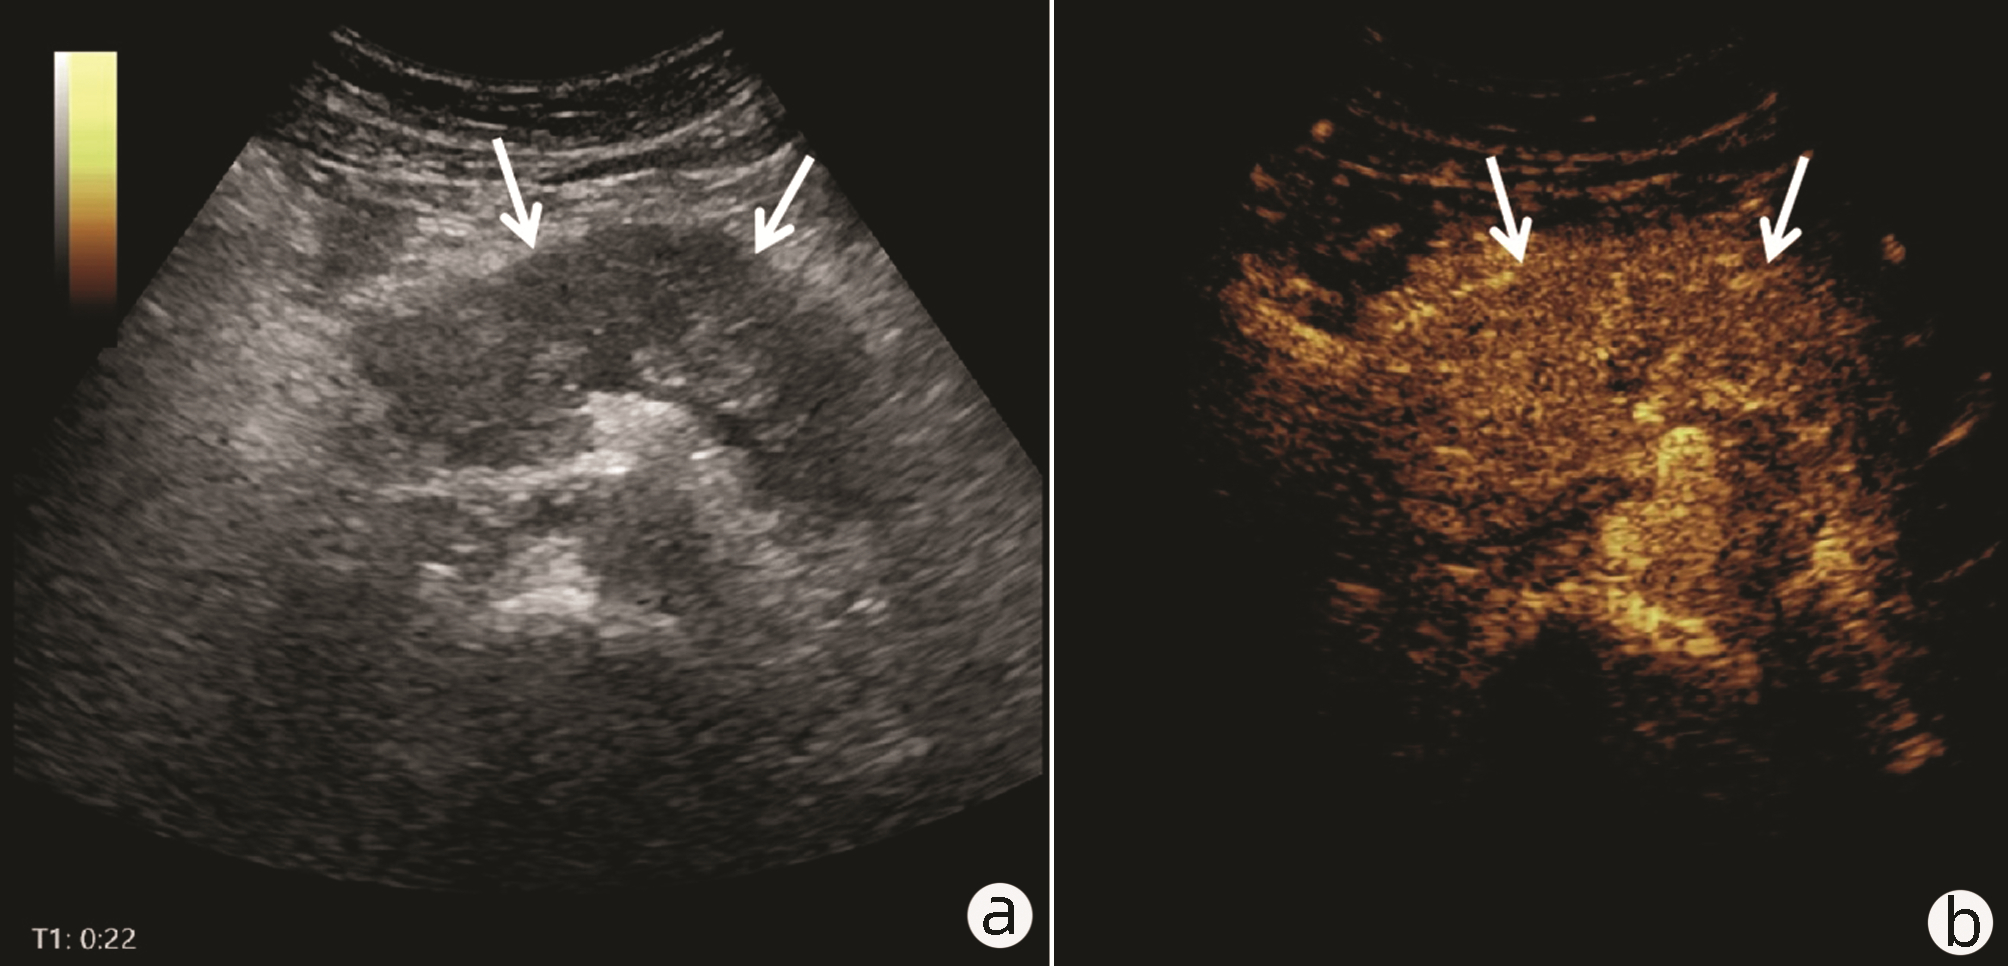

Value of 18F-FDG PET/CT, contrast-enhanced ultrasound, and their combined use in differential diagnosis of benign and malignant pancreatic lesions: A comparative study

Lichun ZHENG, Xiaoming ZHANG, Tianying YU, Jie LI, Xiaoqian DENG, Xiangliu OUYANG

2022, 38(12): 2774-2779. DOI: 10.3969/j.issn.1001-5256.2022.12.017

Abstract(2330) HTML (1630) PDF (3391KB)(64)

Abstract:

Objective  To assess the value of 18F-FDG PET/CT, contrast-enhanced ultrasound, and their combination in the differential diagnosis of benign and malignant pancreatic lesions.  Methods  A retrospective analysis was performed on patients with pancreatic lesions who underwent18F-FDG PET/CT and contrast-enhanced ultrasound who were admitted to Tangshan Gongren Hospital from January 2015 to December 2020. The imaging results were confirmed by pathology examination to evaluate diagnostic sensitivity, specificity, accuracy, positive and negative predictive value. The t-test was used for comparison of continuous data between two groups, and the chi-square test was used for comparison of categorical data between groups.  Results  There were 83 malignant lesions and 25 benign lesions in 108 patients. The sensitivity, specificity, accuracy, positive and negative predictive value were 86.75%, 80.00%, 85.19%, 93.51% and 64.52% for 18F-FDG PET/CT; and 69.88%, 76.00%, 71.30%, 90.63% and 43.18% for contrast-enhanced ultrasound, respectively. The two methods differed significantly in sensitivity and accuracy (all P < 0.05), but not in specificity, negative and positive predictive value (all P > 0.05). When combined with the contrast-enhanced ultrasound, 18F-FDG PET/CT had an increased sensitivity, specificity, accuracy, positive and negative predictive value of 90.36%, 84.00%, 88.89%, 94.94% and 72.41%, respectively, though this was not statistically significant due to the increased signal of blood supply in the lesions.  Conclusion  18F-FDG PET/CT has a better performance than contrast-enhanced ultrasound in the differential diagnosis of benign and malignant pancreatic lesions, and their combination can improve the diagnostic value.